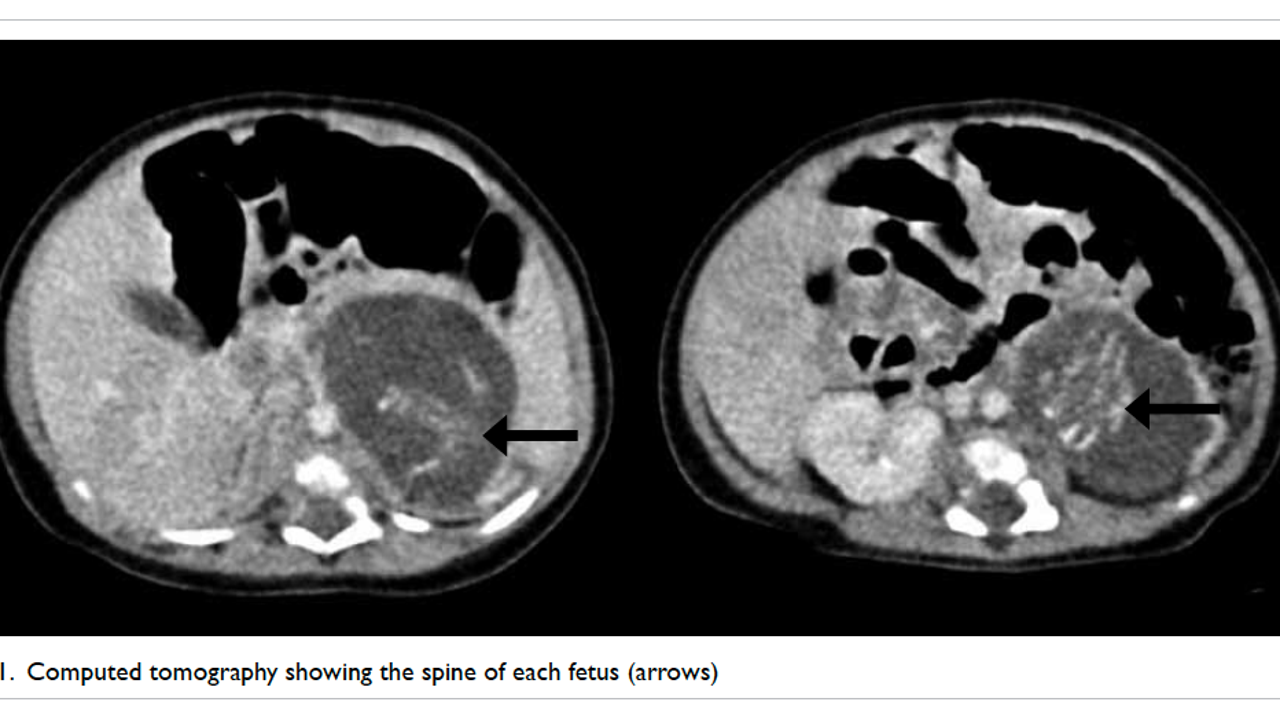

Conception and pregnancy - ScienceDirect, Baby girl born 'pregnant' with twin fetuses | FOX 13 Seattle,